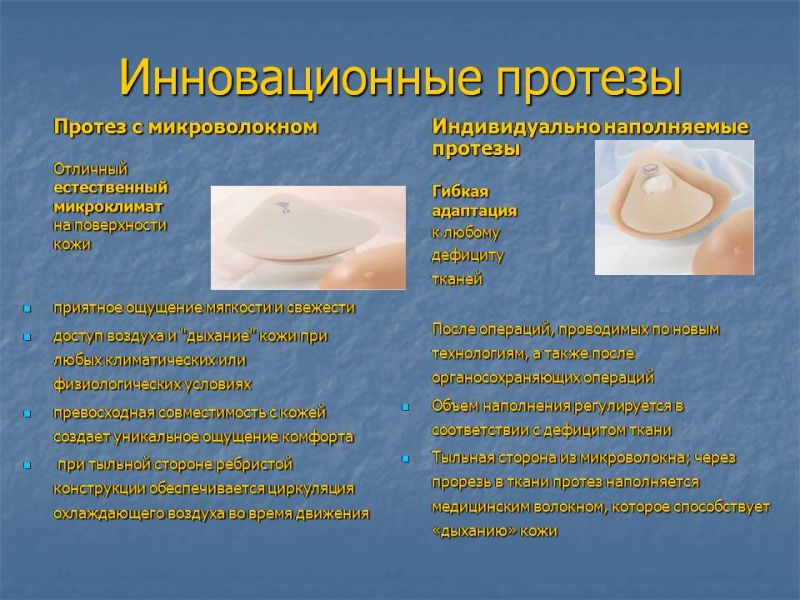

При диагностированной мономастии прибегают к воссозданию недостающей железы посредством реконструктивной хирургии TRAM-лоскутом или установки эндопротеза. С целью иссечения лишних молочных желез проводится мастэктомия, предполагающая их иссечение. Если диагностирована гипоплазия или аплазия, выполняется увеличение груди с использованием современных имплантатов.

С целью иссечения лишних молочных желез проводится мастэктомия, предполагающая их иссечение. Если диагностирована гипоплазия или аплазия, выполняется увеличение груди с использованием современных имплантатов.